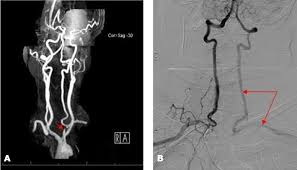

Patients can present with limb claudication and or cerebral symptoms. Bilateral cervical bruits a difference in blood pressure 4550 mmHg between both arms as well as barely discernable radial ulnar and branchial arterial pulses on the right upper limb prompted color duplex which revealed bilateral internal carotid artery stenosis of 75 at each side retrograde flow in his right vertebral artery subclavian-vertebral steal and retrograde flow in his right carotid artery during the midsystolic phase of the cardiac cycle subclavian-carotid steal. Since recognition of this syndrome can lead to successful treatment a review by.

Blood from the contra-lateral vertebral artery is siphoned over at the basilar junction and flows retrograde into the. Right Subclavian Steal Associated with Aberrant Right Subclavian Artery David M.

Subclavian steal syndrome SSS is a condition secondary to an occlusion in the proximal subclavian artery which leads to upper-extremity blood supply to be derived by reversal of flow within the ipsilateral VA. Primary Stenting of Right-Sided Subclavian Artery Stenosis Presenting as Subclavian Steal Syndrome. Blood is drawn from the collateral circulation which results in reversed blood flow in the ipsilateral vertebral artery. The term subclavian steal describes retrograde blood flow in the vertebral artery associated with proximal ipsilateral subclavian artery stenosis or occlusion usually in the setting of subclavian artery occlusion or stenosis proximal to the origin of the vertebral artery. The subclavian steal syndrome is a condition where hypoperfusion of the cerebrovascular system is caused by occlusion or severe obstruction of the proximal subclavian or brachocephalic artery. Alternatively innominate artery disease has also been associated with. Although a low-grade stenosis is usually asymptomatic and may remain unobserved a. The term subclavian steal was coined by Fisher as the reversed retrograde ipsilateral vertebral blood flow was due to the stealing of blood from the posterior cerebral circulation by the subclavian artery. Since recognition of this syndrome can lead to successful treatment a review by.